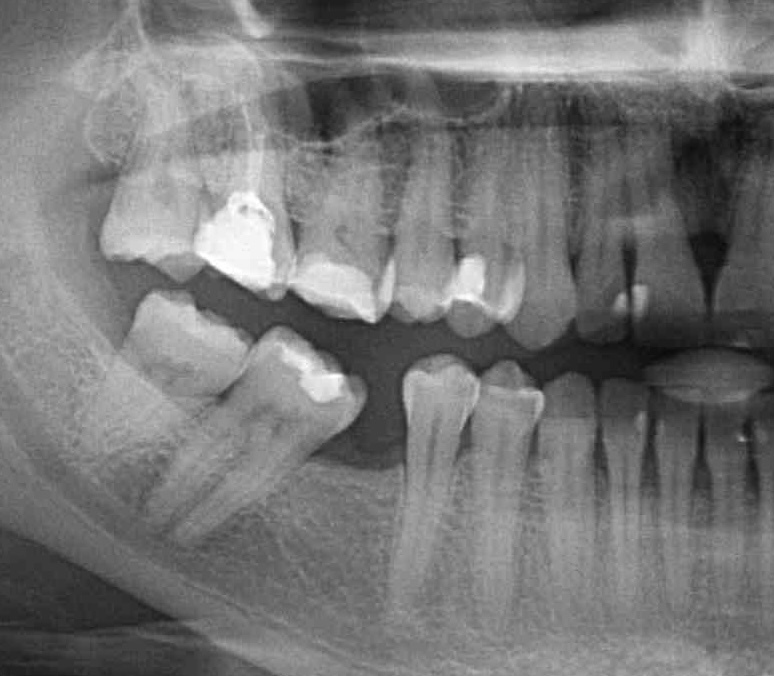

The

patient had his bottom six removed years ago. The teeth had become misaligned

and orthodontic therapy was used to correct the bite of the entire dentition.

Before starting orthodontic treatment, the teeth must be healthy, the

periodontal tissues must be free of inflammatory changes. In addition, it is

very important to master meticulous oral hygiene.

After 6 months of successful

orthodontic treatment, we were finally able to place the implant and the

provisional crown. After 4 months of ingrowth, aligners were removed and a full

ceramic crown was placed. The treatment was successfully completed!✋🏽😉